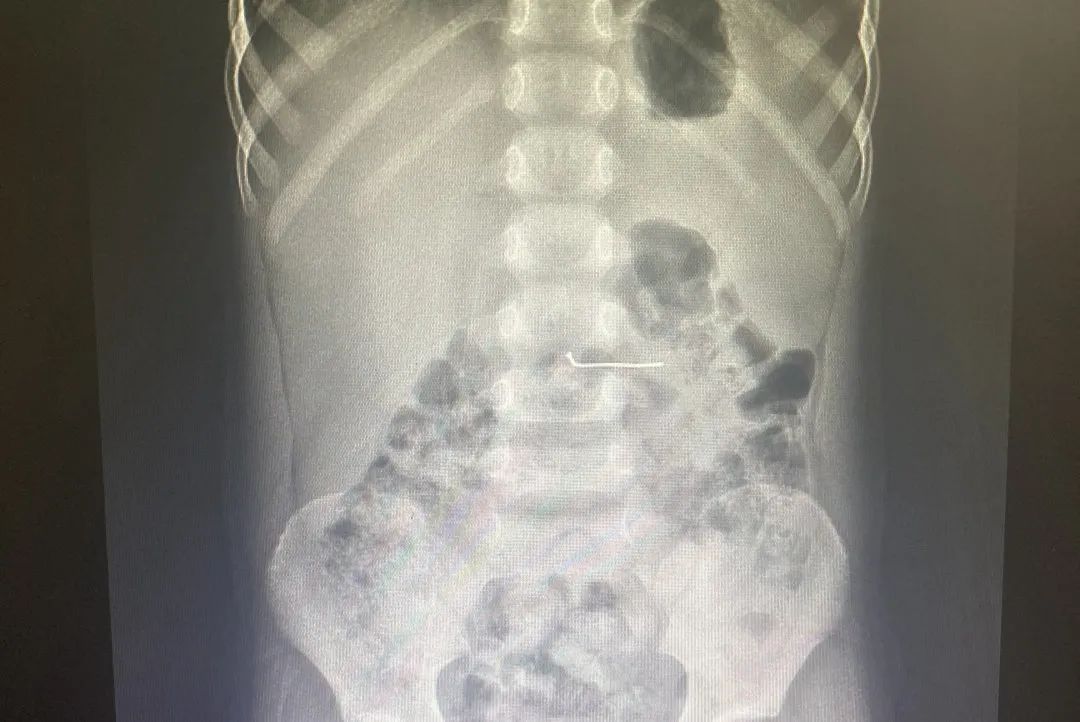

△经摄片可清晰看到气钉在男童体内

当天下午2点多,沛县一名5岁男孩在玩耍过程中,误将1枚3厘米长的气钉吞下。家长发现后,立即将孩子送至当地一家医院救治,经摄片发现该气钉横在孩子的胃内。当地医生告知,带有尖锐头端的气钉随着胃蠕动,随时可能划破孩子娇嫩的黏膜甚至大血管,造成消化道出血,如果钉子滑入小肠极有可能刺破肠壁,引起肠穿孔、腹膜炎,甚至危及生命。

在医院总值班姬怀雪和儿科主任关凤军的协调下,儿科、消化内科、麻醉科、消化内镜中心联合行动,半个小时内所有人员准备就绪。经急诊儿科拍摄的片子显示,气钉位置较当地医院摄片时已经明显下降,极大可能已经进入小肠,胃镜治疗的可能较低。儿科主任沈栋林凭借经验,认为孩子年龄小,气钉长度较长,异物通过幽门有一定的困难,有尚在胃内的可能。